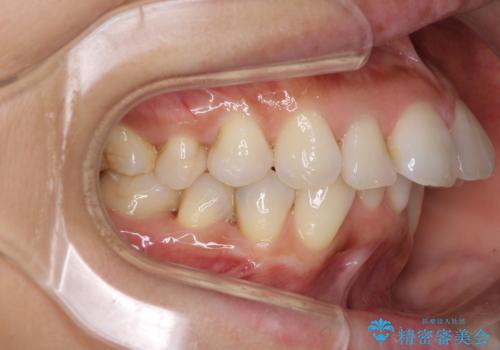

- 上下の歯のがたつきを主訴に来院されました。

上下の前歯の叢生とかみ合わせが深い過蓋咬合という状態でした。

上下左右の歯を1本ずつ抜歯して、ワイヤーにて矯正を行いました。